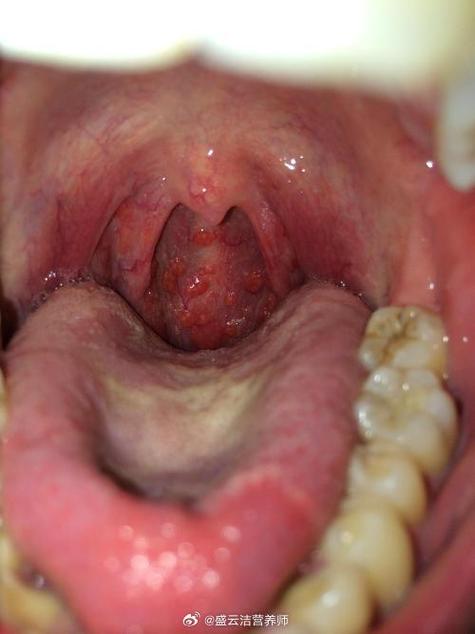

扁条体发炎吃哪些食物能缓解? 宜吃的食物(推荐清单) 这些食物通常具有清淡、柔软、温凉、富含维生素和水分的特点。(图片来源网络,侵删) 清流质/半流质食物 这是发炎期间的“黄金选择”,能最大程度减少对咽喉的摩擦和刺激。 温开水:最重要的!保持充足水分可以稀释痰液,缓解喉咙干燥,冲刷病菌。 清淡的汤羹: 蔬菜汤:如冬瓜汤、白菜汤,...